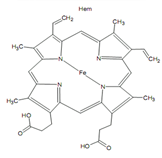

• Vér vas tartalma - Válasz 18

• Vashiány és pótlása